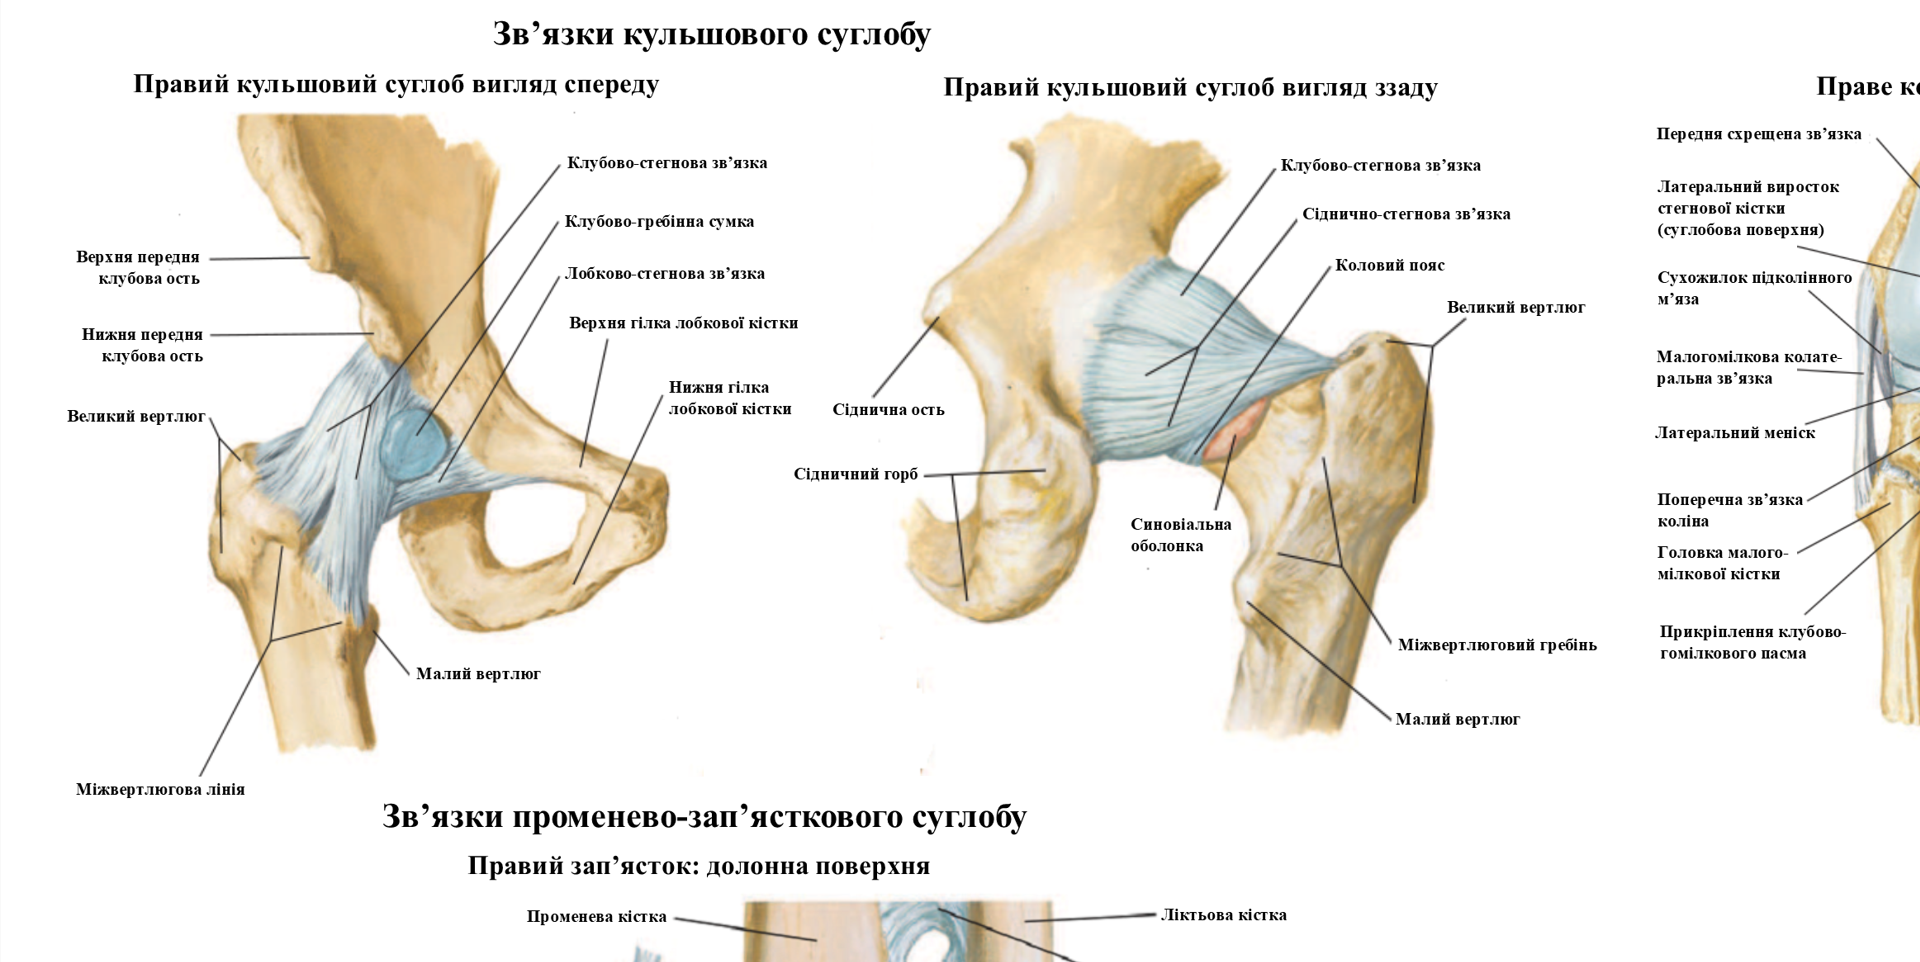

Диаграммы и схемы движения в суставах человека